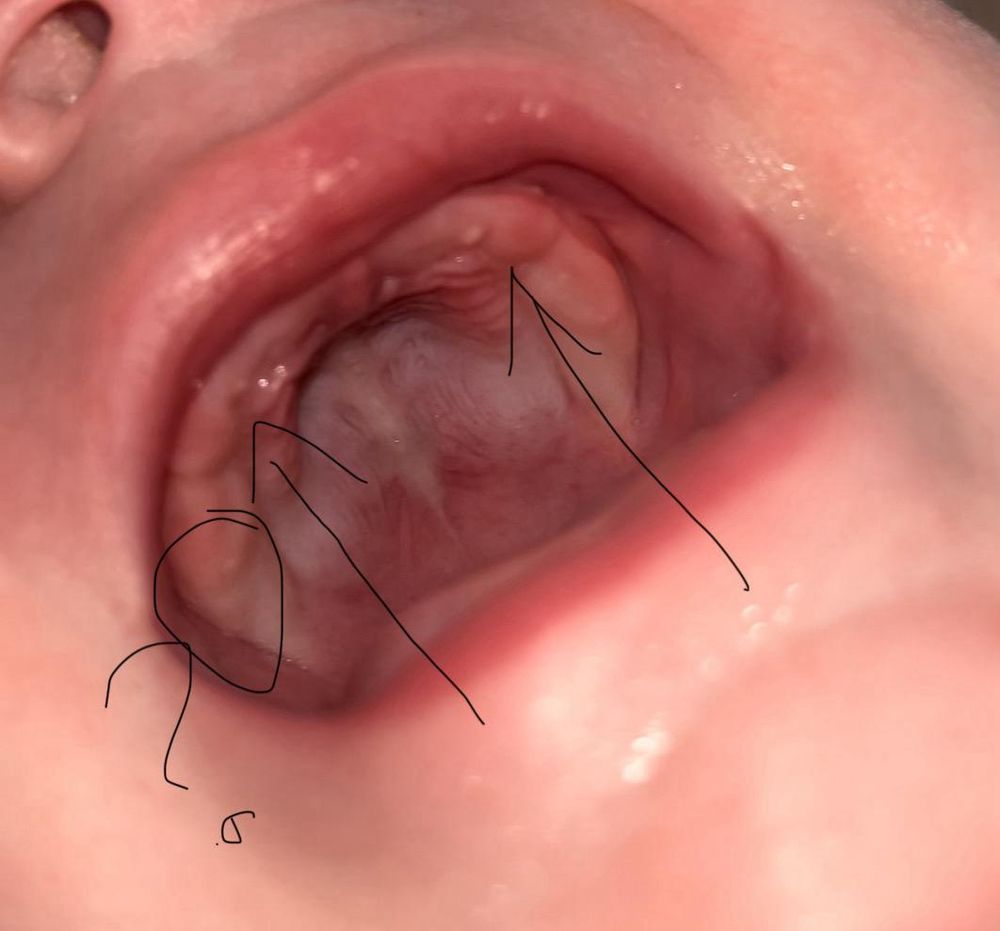

Я не вижу признаков по десне🤷🏼‍♀️ Может, нижние все-таки? Посмотрите повнимательнее резцы нижние, если подозреваете зубы.

Ничего не лезет, это нёбо. Верхние немного не оттуда вылазят

Елизавета, странно, педиатр сейчас по этому фото сказала что двойки или тройки лезут.

Татьяна, это жемчужинки просто)